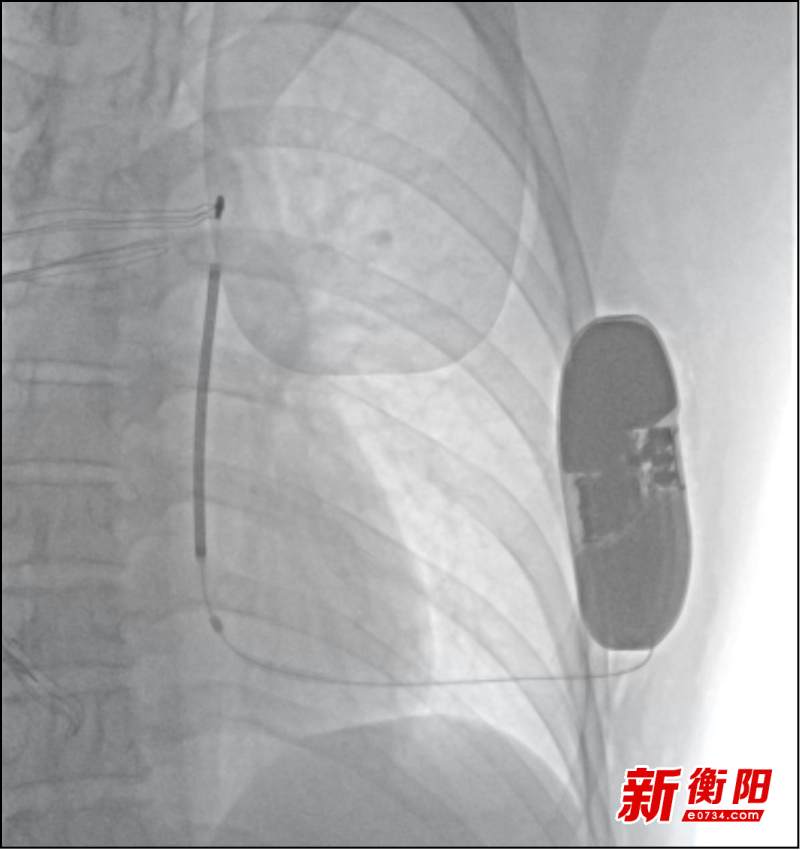

△S-ICD植入术后影像

因患者鲁先生非常年轻,无缓慢性心律失常发生,同时又存在解剖变异“永存左上腔”,TV-ICD植入存在技术难度且增加了并发症风险,经马小峰及电生理团队充分评估并与患者及家属沟通,最终决定进行S-ICD植入术。与TV-ICD相比,S-ICD只植入于皮下,不进入血管和心脏,能够避免可能造成的血管损伤,减少潜在的系统感染风险,降低导线相关并发症。在医院麻醉科、ICU的通力配合下,手术历时1小时顺利结束,患者的救治工作圆满完成。